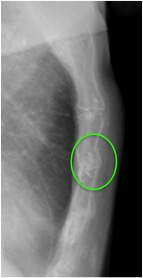

CASO: Febrícula y tos de 4 días de evolución.

Hallazgos:

- En la placa PA se observa una asimetría en los hilios pulmonares, el hilio izquierdo tiene una densidad aumentada.

- Tras examinar la placa lateral se observa un aumento de densidad en la columna que puede ser compatible con una condensación, es el signo de la desnificación vertebral.

SIGNO DE LA DENSIFICACIÓN VERTEBRAL: En la radiografía lateral normal, la densidad de la columna torácica tiende a disminuir desde la parte superior hasta el diafragma; la alteración de ese patrón por la presencia de una densidad superpuesta a la columna, indica la existencia de una consolidación pulmonar. Este signo adquiere especial valor cuando en la proyección posteroanterior la consolidación está oculta en el espacio retrocardíaco o en la base pulmonar.